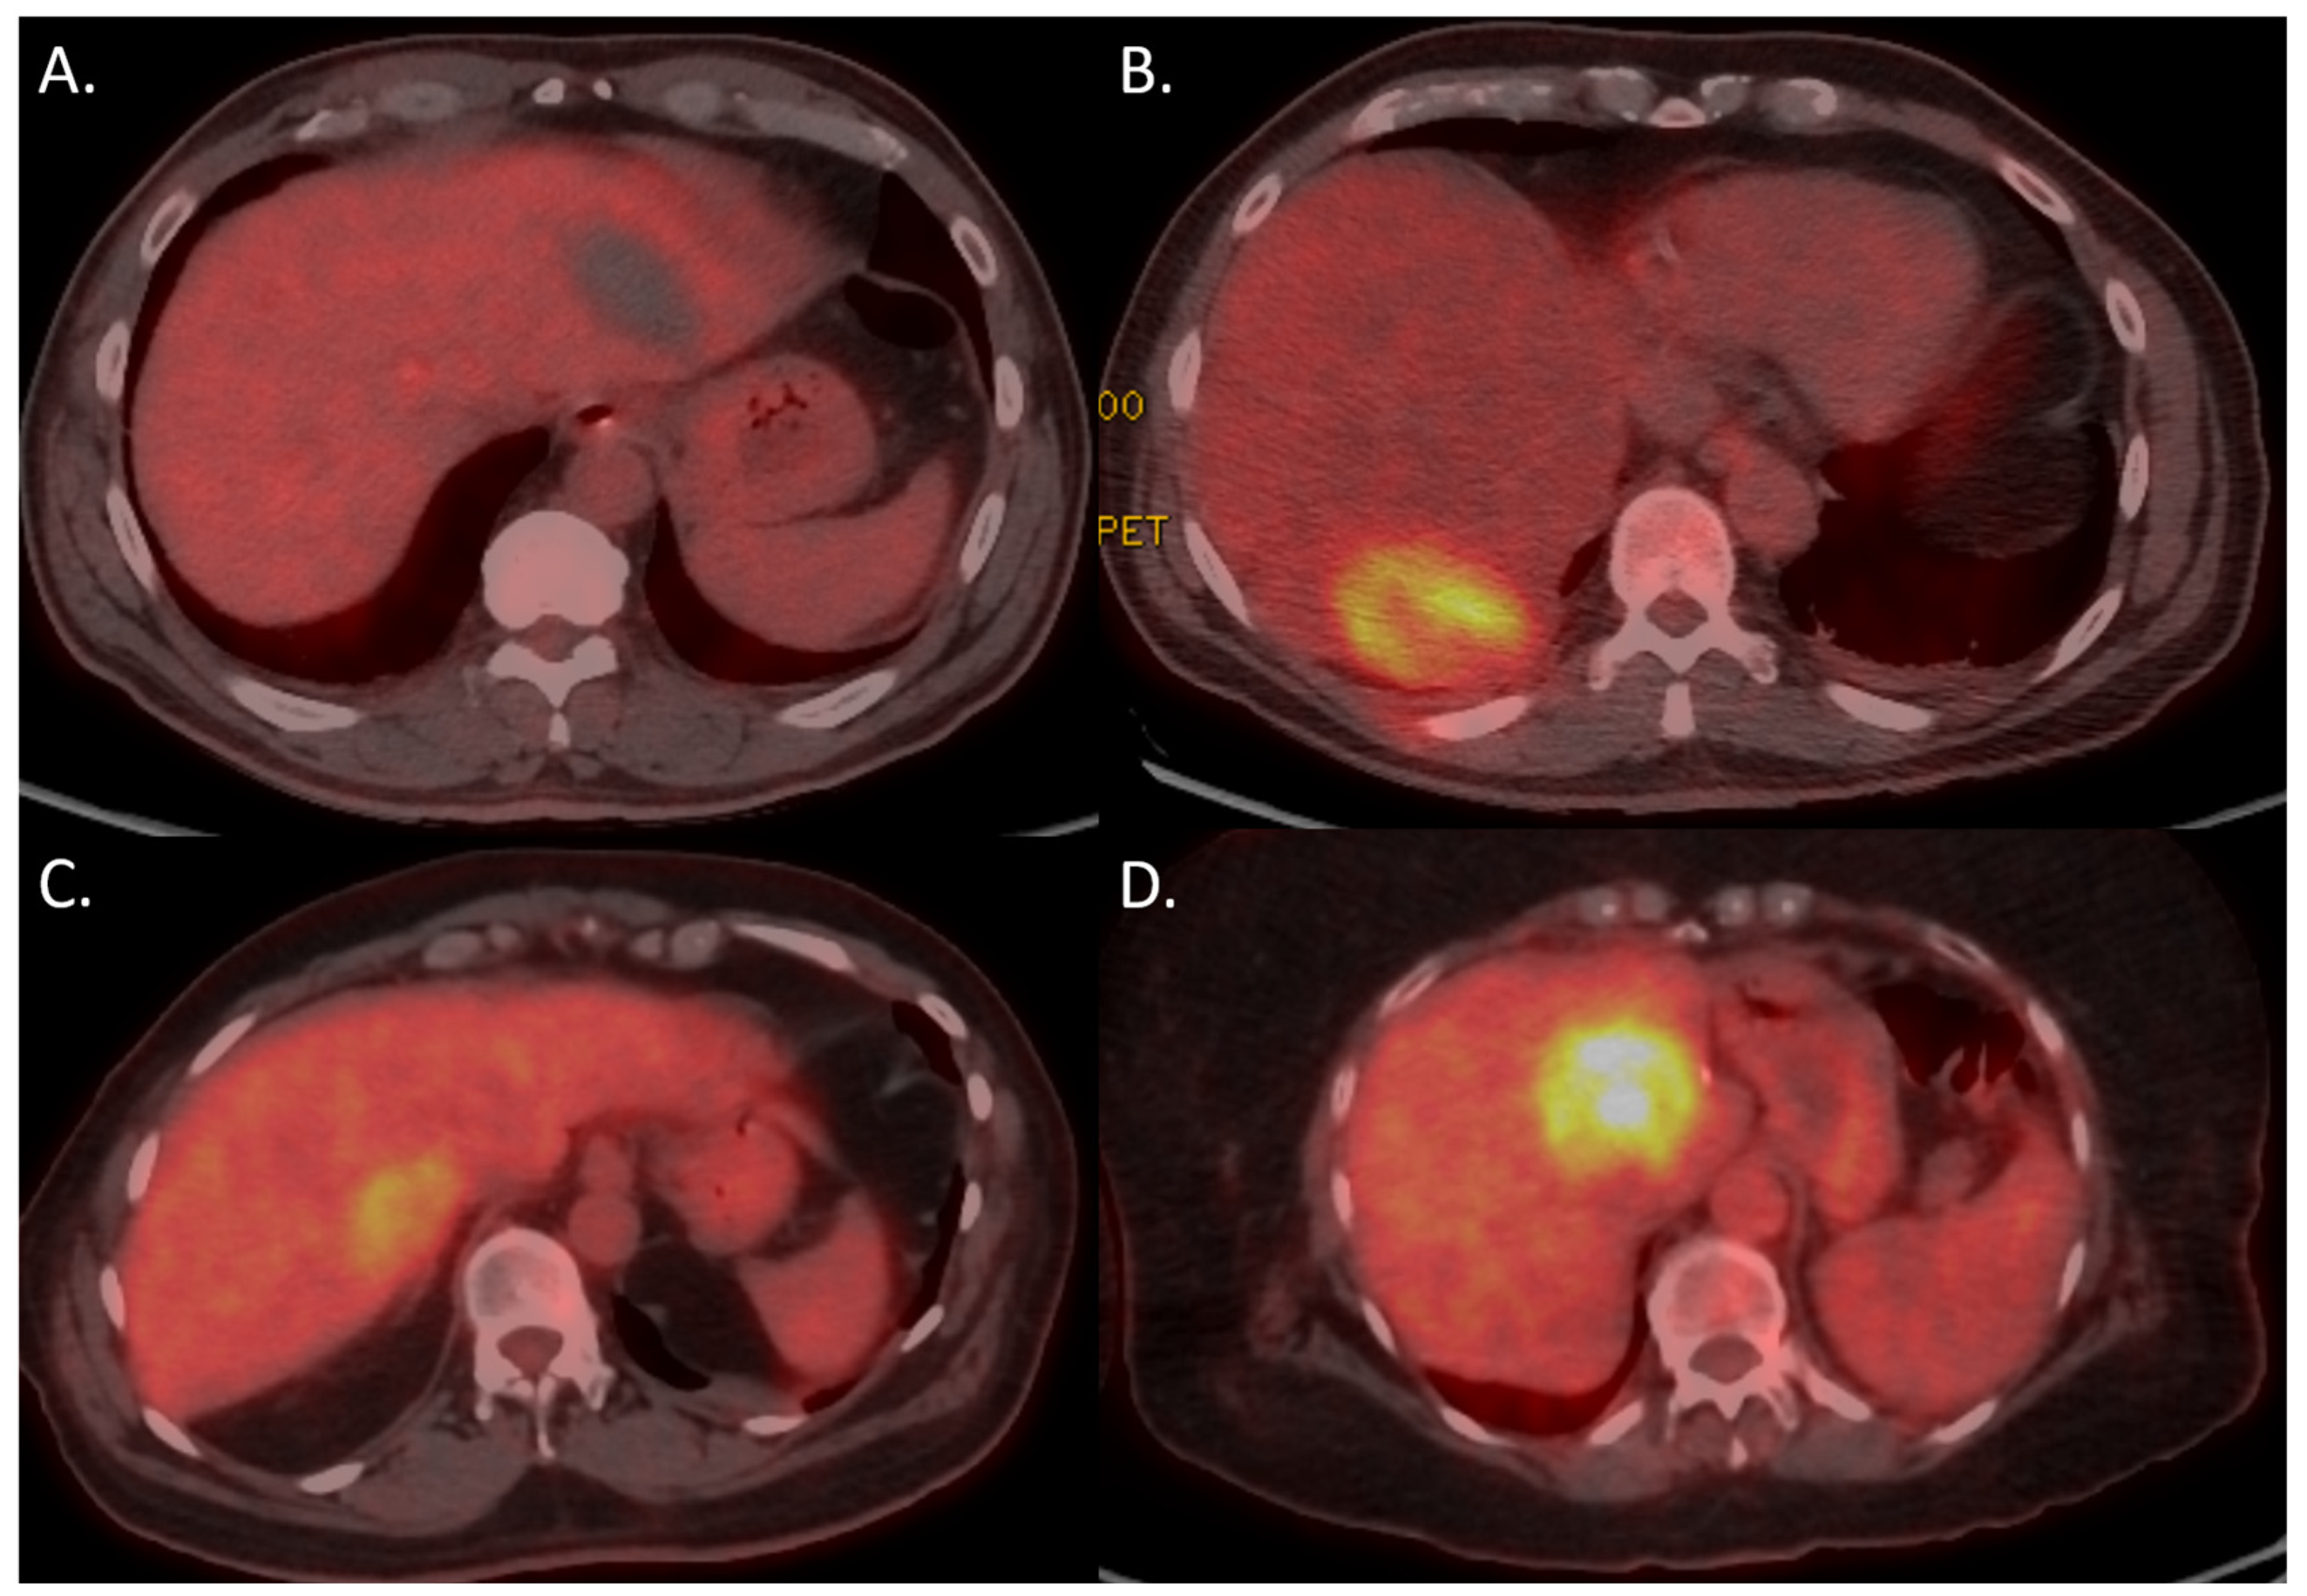

3.4. Multivariable Analysis